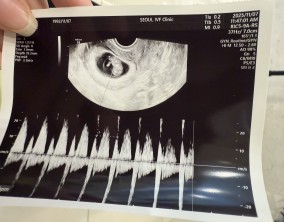

눈물로 실감한 아홉 번째 주

이경훈 원장님은 검사를 통해 나온 수치와 결과에 대해 자세히 설명해 주시고, 상황에 맞는 여러 방법을 함께 제시해 주셔서 큰 신뢰와 감사함을 느꼈습니다. 불안을 혼자 짊어지…